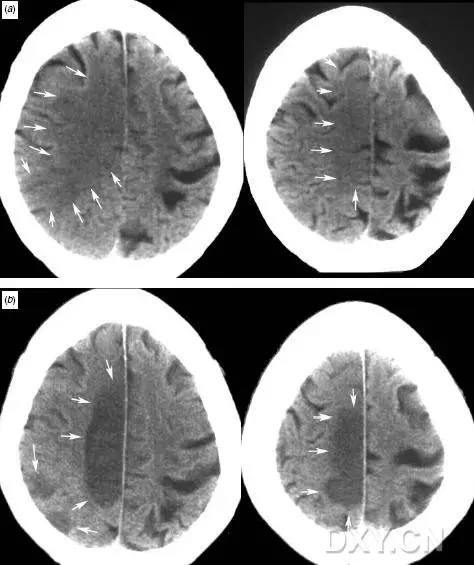

病例二

患者突发左侧偏瘫,a图为发病后2小时CT示:右侧脑室受压变形,右侧大脑中动脉供血区皮质水肿、脑回模糊、脑沟变浅或消失;

b图为发病6天后的CT,可见右侧脑室旁皮层下梗死,伴右侧大脑中动脉供血区皮层水肿